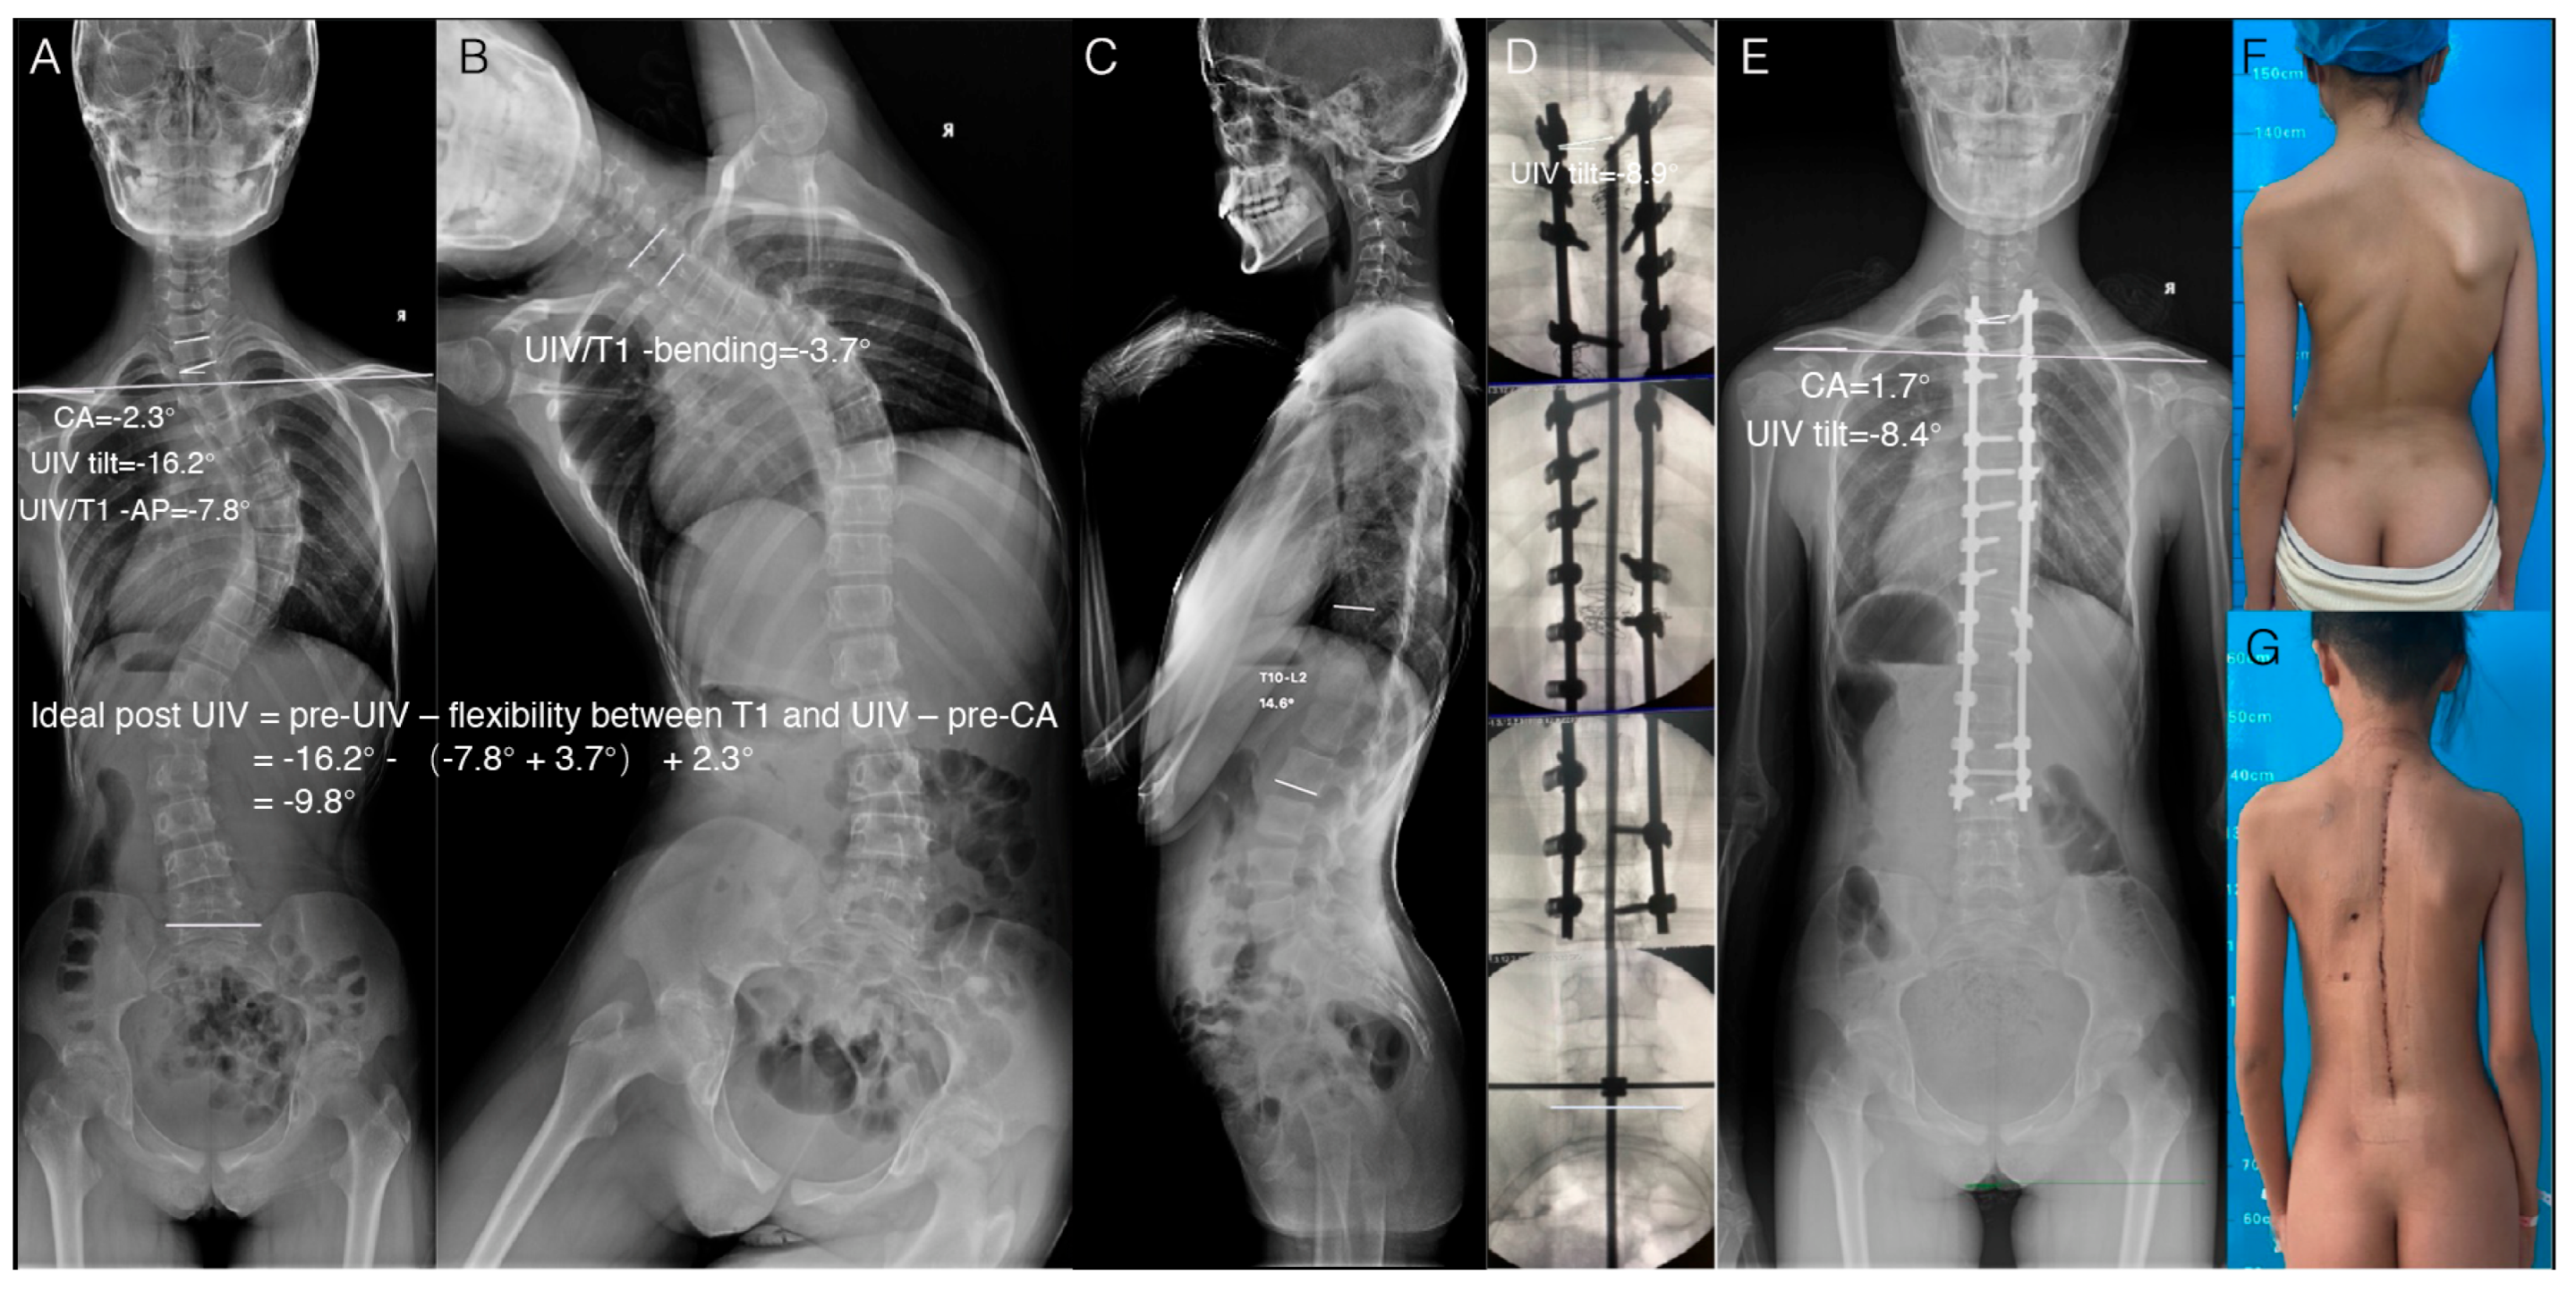

2.4. Verification of the Feasibility of This Method in Clinical Practice